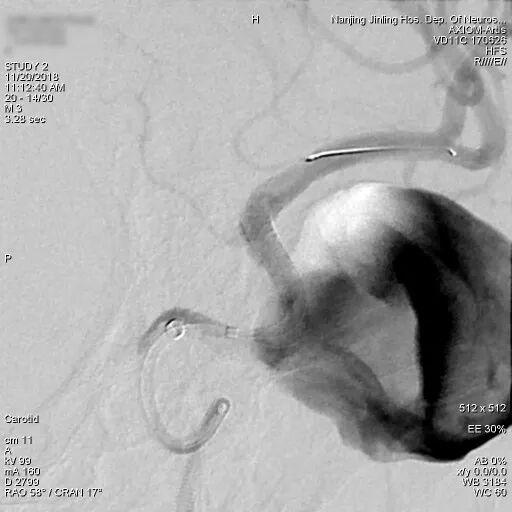

患者取平卧位,气管插管全麻,右侧股动脉穿刺,置入6F 70cm长鞘至左侧颈总动脉,5F Navien中间导管在Marksman引导下超选至动脉瘤近端,行3D旋转造影显示:左侧颈内动脉海绵窦段大型血栓性动脉瘤。

为什么要用到微导管张鑫教授:“球囊锚定微导管辅助到位”技术在Pipeline Flex治疗复杂动脉瘤手术中的应用_https://www.jmylbn.com_新闻资讯_第4张

3D旋转造影

显影部分动脉瘤大小约31.6*23.1mm,瘤颈宽6.4mm,载瘤动脉远端直径约为2.93mm,近端约为2.89mm。根据造影情况决定行血流导向装置置入术,选择Pipeline Flex 3.0mm*35mm。